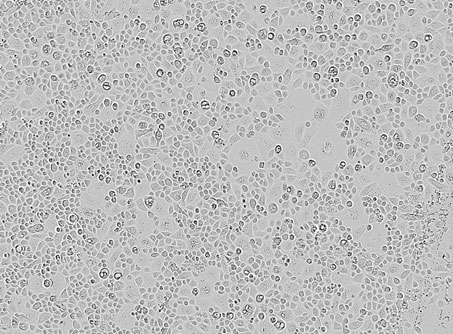

Figure 4.

Limbal epithelial cells enriched in stem cells.

[Source: Dr. Ljubimov]